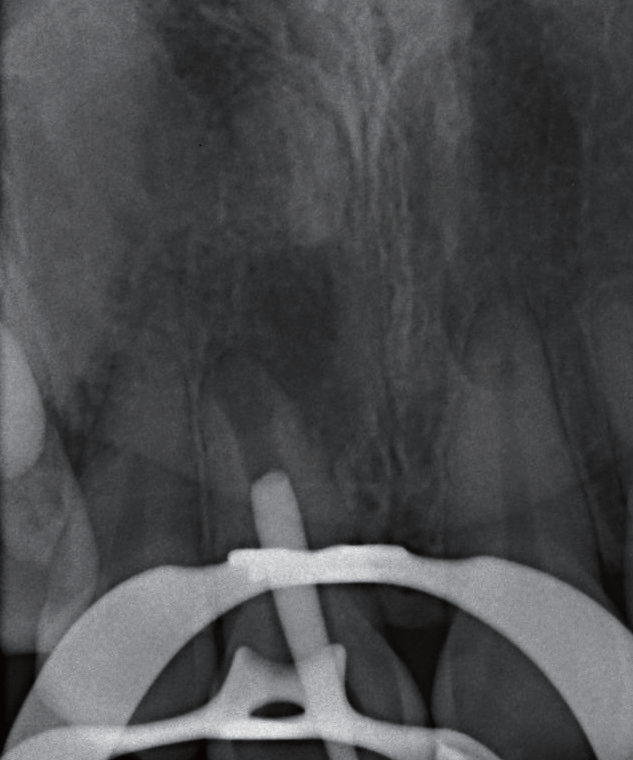

治疗过程   显微镜下可见11牙冠唇侧(图4)和腭侧(图5)存在数个大小深浅不一的裂纹,开髓至牙本质层(图6),患者表示无任何不适,开髓后就闻到髓腔内有臭味溢出,但患者依然无疼痛,经确认11牙髓已坏死(图7)。随后进行根管预备、次氯酸钠溶液冲洗、纸尖干燥(图8)、试主尖(图9),因根尖呈开口状,决定将牙胶尖四周覆盖MTA进行根尖封闭(图10~12),X线片显示根充密合,后续封闭根管中部和冠部(图13),并用光固化复合树脂充填11牙冠(图14),调磨抛光,再次拍摄根尖X线片确认治疗结果(图15),嘱患者定期复查,观察患牙。

图10 以自制MTA 覆满的牙胶尖,尝试封闭呈喇叭状开口的根尖

图11 运用施德氏根充法,将特制牙胶尖压实

图12 不断重复加热、软化覆满MTA 的牙胶尖,以垂直加压法将其填满根尖